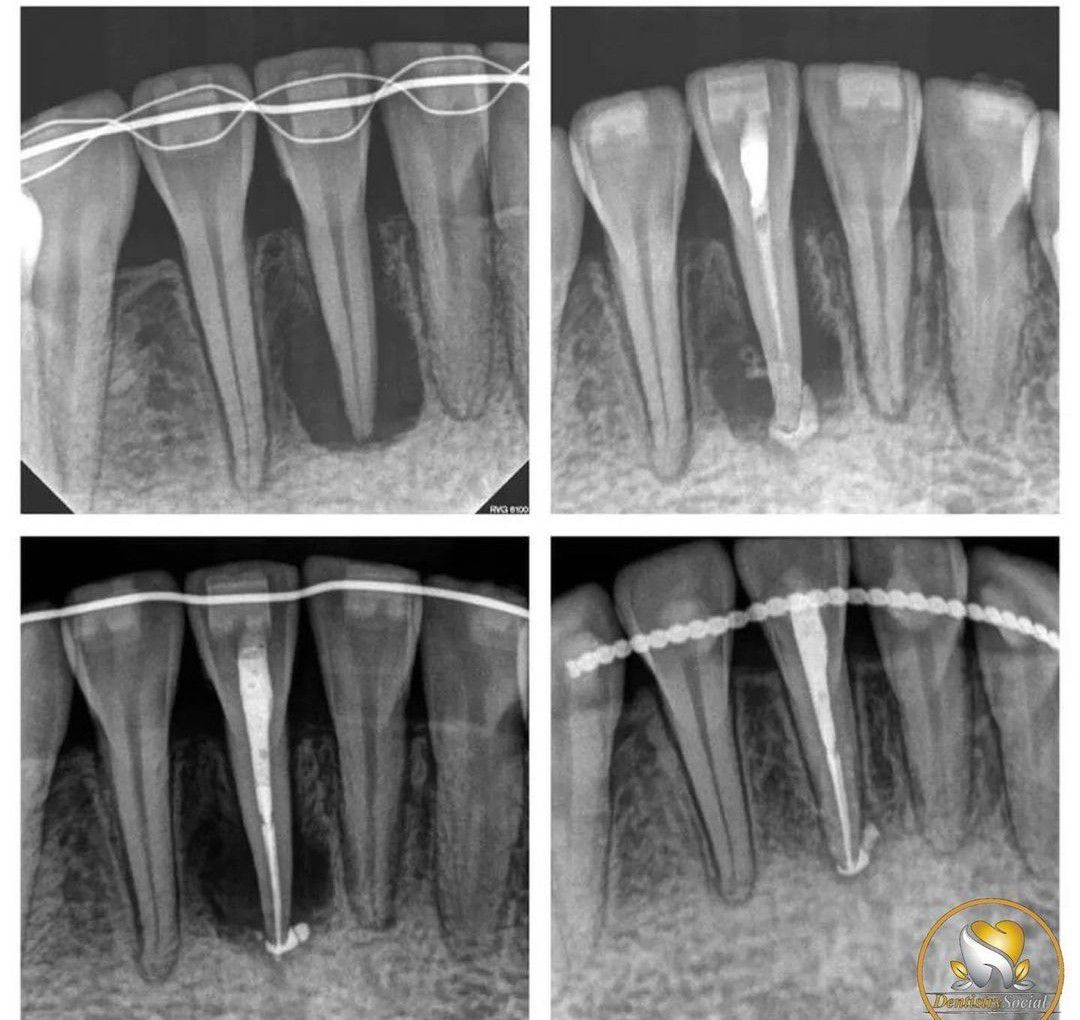

Healing process of Endo Procedure

Here you can appreciate the healing process of Endodontic procedure.